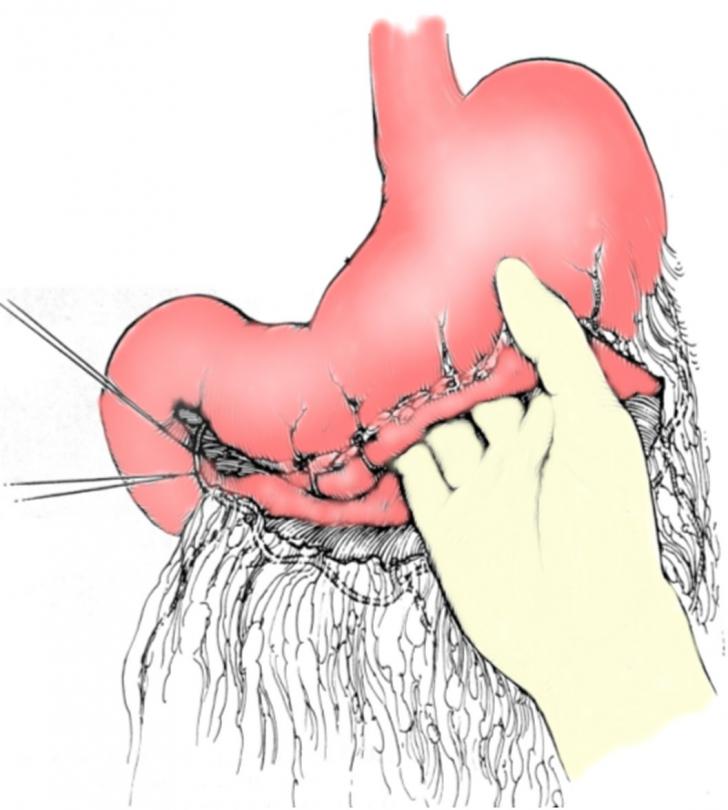

REZECTII GASTRICE - CHIRURGIE

REZECTII GASTRICE - CHIRURGIE I. DEFINITIE Rezectia gastrica este interventia chirurgicala prin care se realizeaza indepartarea a 2/3 distale din stomac (3/5 din cel dilatat); in segmentul indepartat se include si segmentul juxtapiloric al pCiteste tot ... 5025 cuvinte

Dimensiune mare

+ cu imagini |